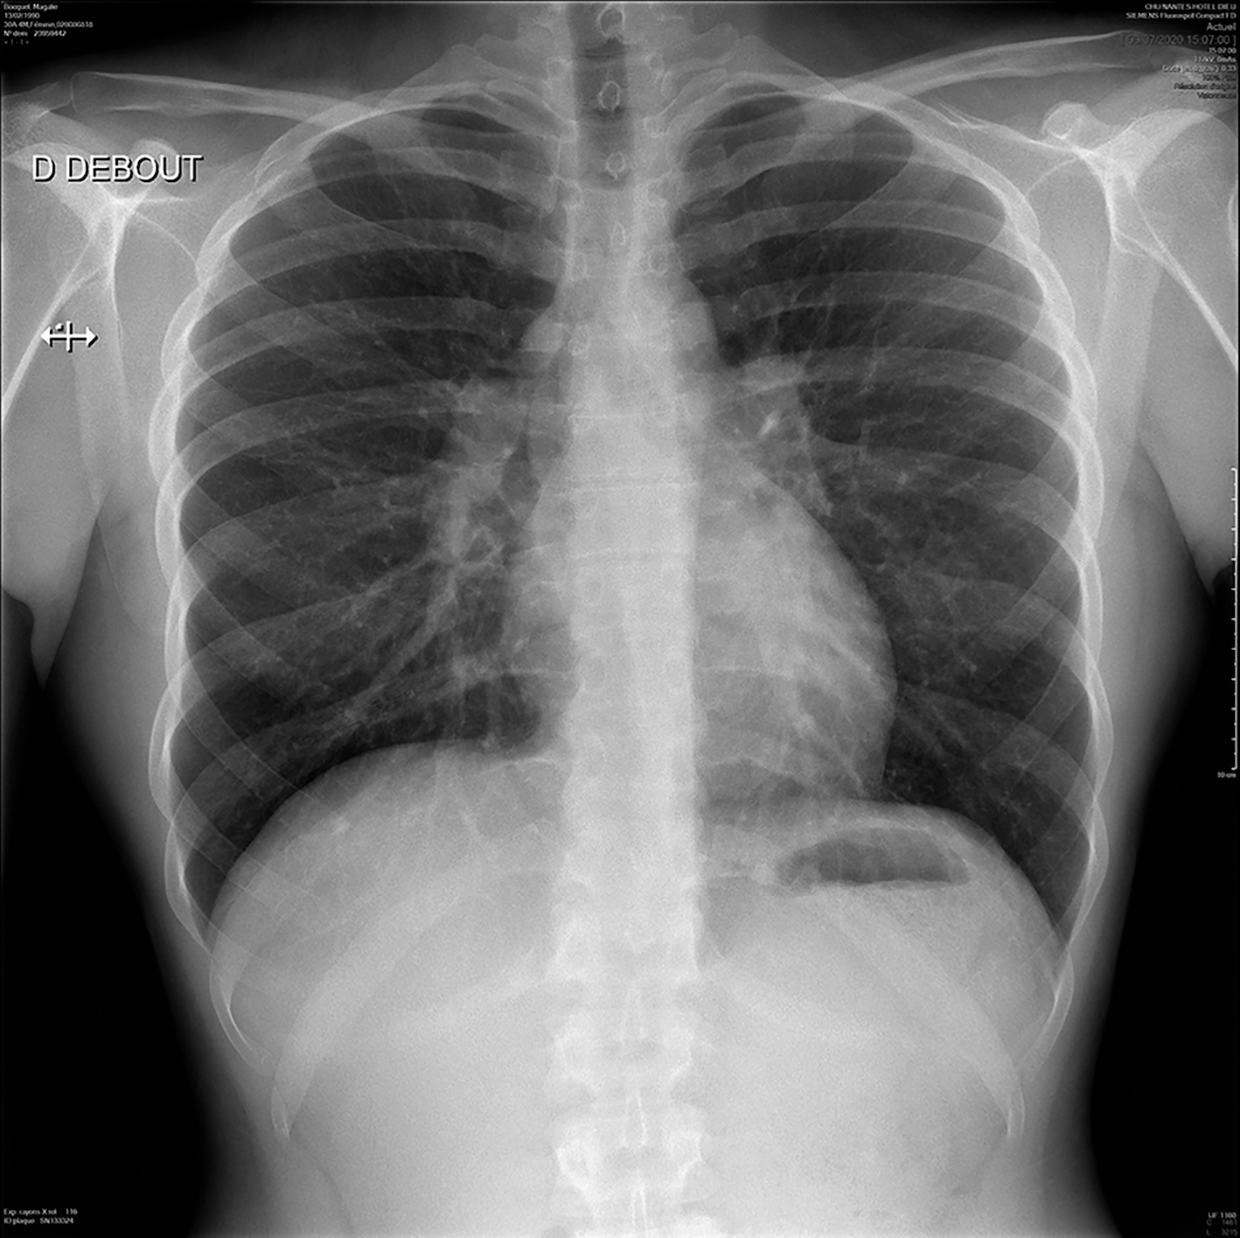

Radiographie de thorax

La radiographie de thorax doit être systématique. Il existe cinq types d'atteinte radiologique :

• stade 0 : image thoracique normale au cours d'une sarcoïdose extrathoracique (20 % des malades) ;

• stade 1 : adénopathies intrathoraciques isolées, non compressives, le plus souvent asymptomatiques (50 %) (fig. 23.4) ;

• stade 2 : image infiltrative diffuse avec adénopathies intrathoraciques ;

• stade 3 : image infiltrative diffuse sans fibrose (25 %) ;

• stade 4 : lésions irréversibles fibro-emphysémateuses (5 à 8 % des cas).

Fig. 23.4. Adénomégalies médiastinales bilatérales sans atteinte pulmonaire interstitielle, dans une sarcoïdose pulmonaire au stade 1.